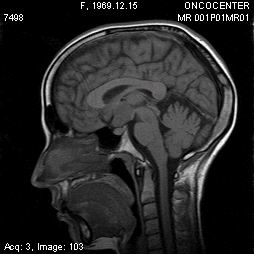

Описываем клинический случай стереотаксической брахитерапии, выполненной в Уральском межтерриториальном нейрохирургическом центре (ГБУЗ СО Свердловский областной онкологический диспансер), пациентке К. 31 год с глиальной опухолью диэнцефальной области (дна III желудочка). Данные МРТ головного мозга представлены на слайдах.

Этапы стереотаксической брахитерапии представлены на слайдах ниже.